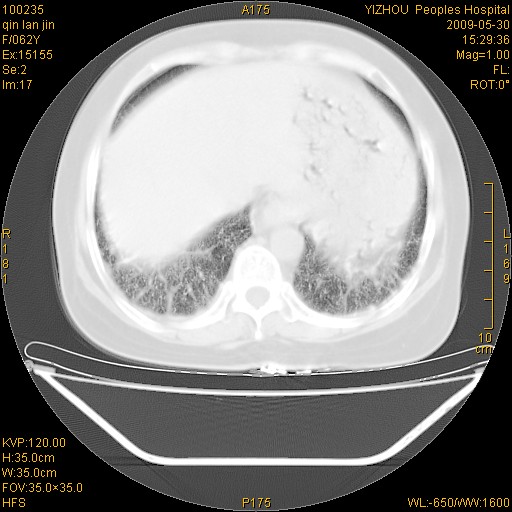

标题: CT20268:肺泡癌?间质性肺炎? [打印本页]

标题: CT20268:肺泡癌?间质性肺炎?

女,62岁,近二年经常咳嗽,近二个月,消瘦、乏力。

前面一张胸片是今天照的,后面一张胸片是去年9月份的。

弥漫性双肺间质纤维化。

两肺弥漫性间质性病变(间质性肺炎伴肺间质纤维化?)。

间质性肺炎伴肺间质纤维化。

纵隔淋巴结大,须排外癌性淋巴管炎